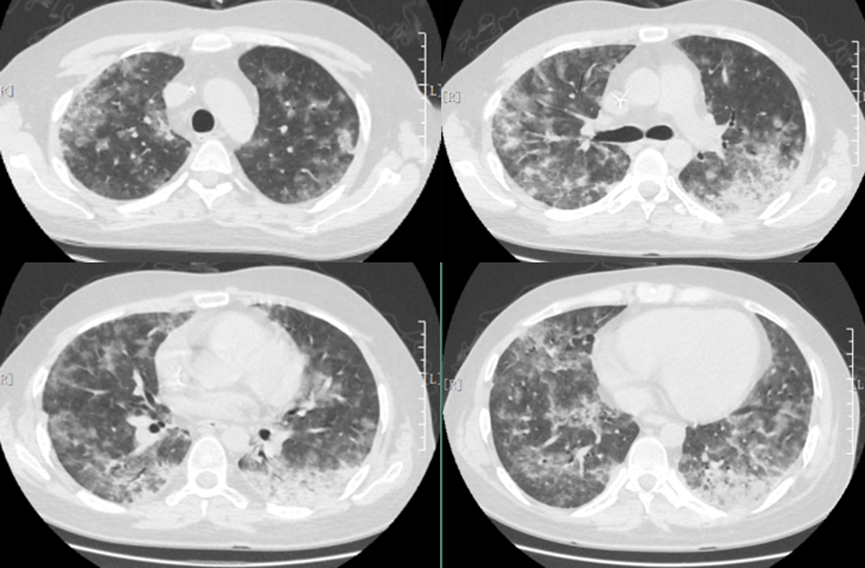

• 胸部CT:双肺磨玻璃样改变(图1)

图1  患者胸部CT(2018年9月13日)

胸部高分辨率CT(high-resolusion computed tomography,HRCT)检查是诊断PJP的重要手段,早期典型的胸部HRCT表现为双肺由中心向外周分布的对称性多发的弥漫性粟粒状、斑点状阴影,边界清晰。炎症急性期HRCT可见以肺门为中心的双侧对称向外分布的弥漫性磨玻璃影,胸膜下较少受累及,呈典型的月弓征表现。恢复期伴随组织修复,纤维结缔组织增生,HRCT呈间质纤维化改变,双肺下叶间隔明显增厚,条索影、网格影等改变。其中肺气囊是PCP较常见的影像学表现,表现为磨玻璃影、间质病变中的薄壁空腔,破裂可引起自发性气胸、纵膈及皮下气肿,少见表现包括有结节、实变、纵隔淋巴结肿大、胸腔积液等。合并其他病原菌感染或有肺部基础疾病者,影像学表现不典型。